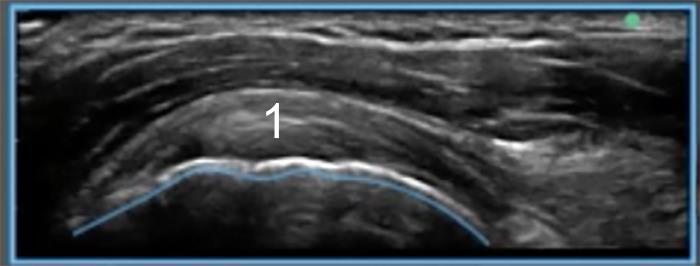

Shoulder Greater Tuberosity Anatomy 1 Longitudinal Bony Profile Image

Anterior over biceps tendon at the level of the humeral head

1. Biceps tendon (longitudinal) as it emerges from its origin in the glenohumeral joint to enter the rotator cuff interval